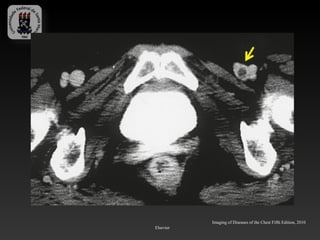

-Linfonodos mimetizando tromboembolismo pulmonar

Imaging of Diseases of the Chest Fifth Edition, 2010 Elsevier